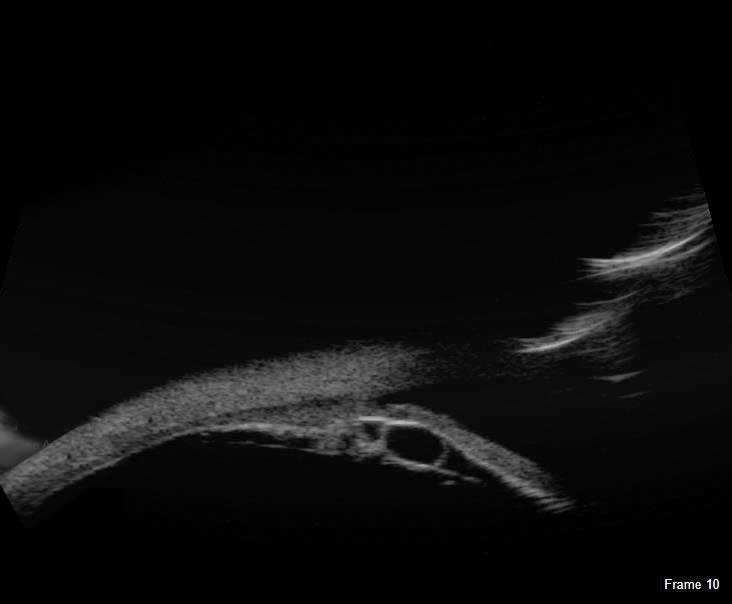

The redesigned B-Scan Probe, new with the Flex, provides clear imaging of the posterior segment of the eye, even when optical clarity is compromised.

The Scanmate Flex B-Scan probe enables clinicians to capture clear and precise images and videos of the posterior segment of the eye. Ultrasonic B-scans are effective, even when opacities (such as dense cataract, blood, or anatomical structures) are present which obscure optical technologies.

The B-Scan probe is available in both 12.5 MHz and 20 MHz frequencies. Among the on-screen tools are calipers to measure structures, an area measurement tool and an annotation tool that gives you a way to indicate pathologies on the image.

B-Scan Diagnostic Applications

The Flex B-Scan delivers clear images of the posterior portion, even when optical clarity is compromised. B-Scan imaging can aid the evaluation of:

- Retinal Detachments

- Vitreous Detachments

- Vitreous Humor Pathologies

- Staphylomas

- Posterior Segment Pathologies

- Choroidal Pathologies

- Optic Nerve Pathologies

- Scleral Thickening